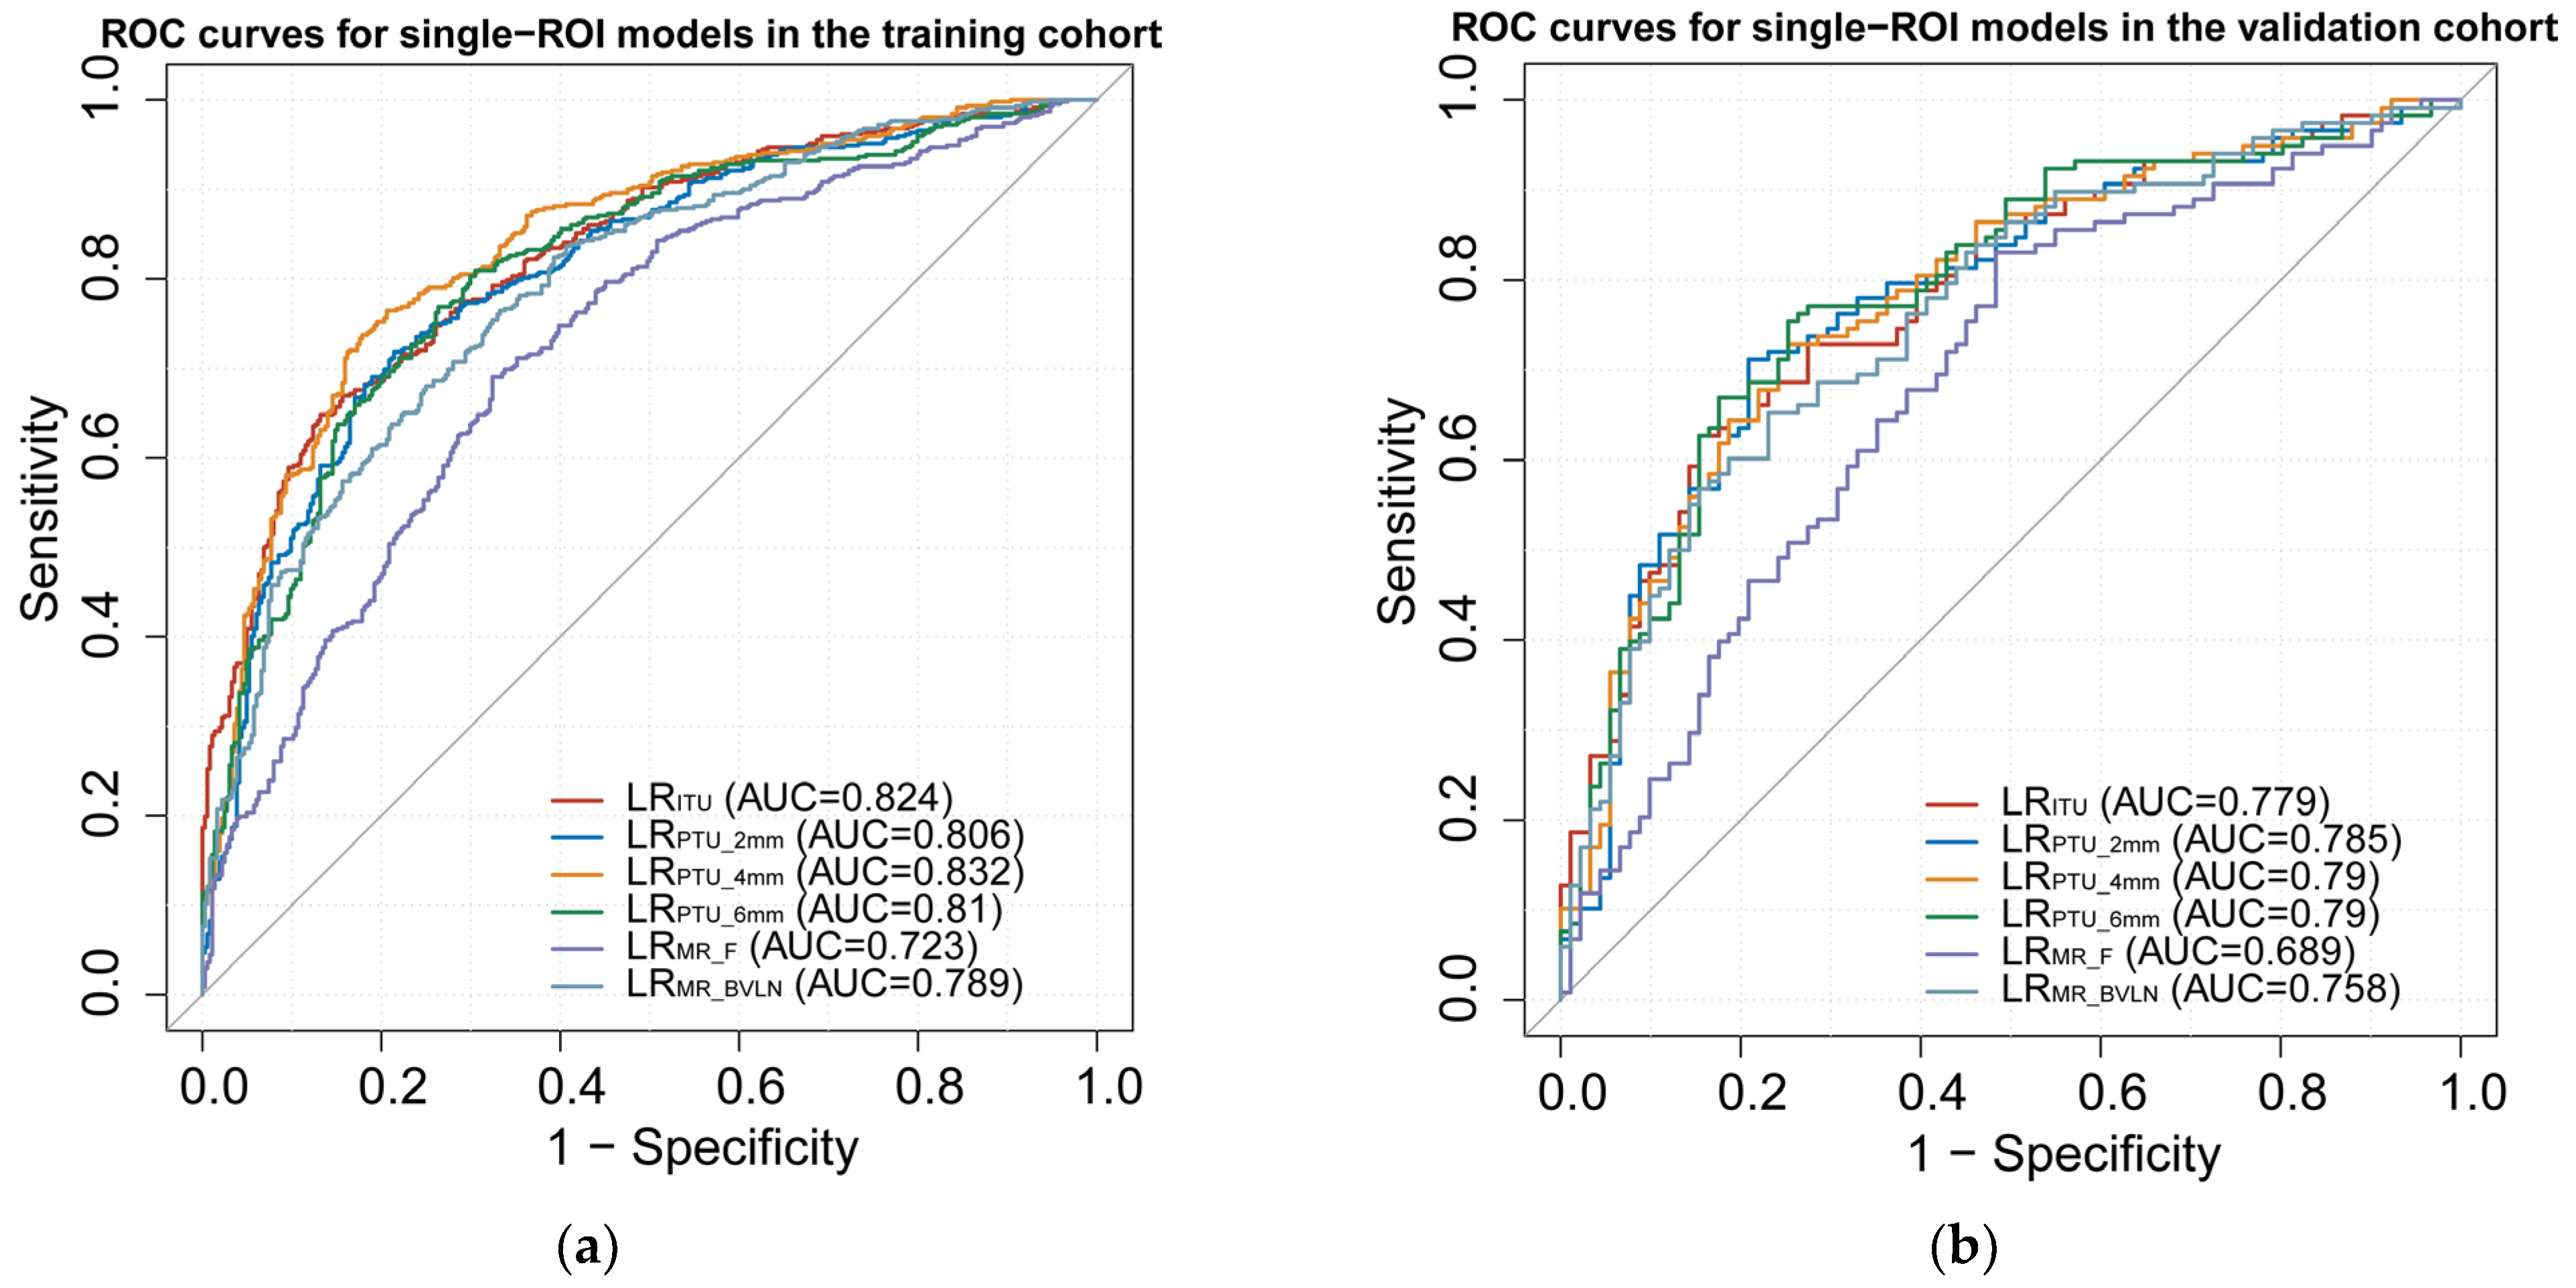

3.3. Model Construction and Assessment

3.4. Clinical, Radscore, and Cli–Radscore Models